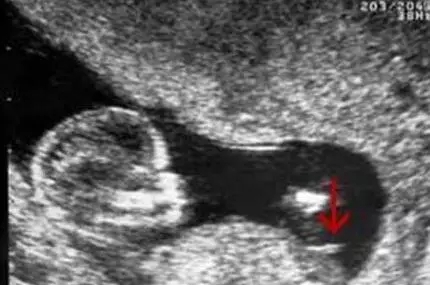

B超图分辨男宝女宝性器官

在照B超的时候,医生都会从屁股底下照看看左右的大腿,仔细观察的话可以发现在图中会有“谜之小凸起”,上图中的箭头所指就是,看到这里相信不用我说各位也一定看出来是一位小王子了。